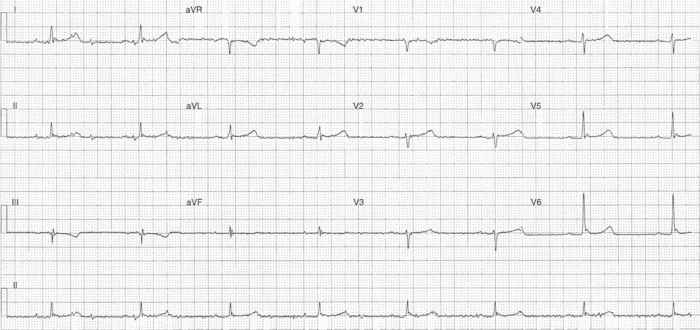

ECG Case 305

The following ECG is from a 62-year-old male who presented with 90 minutes of central chest pain...